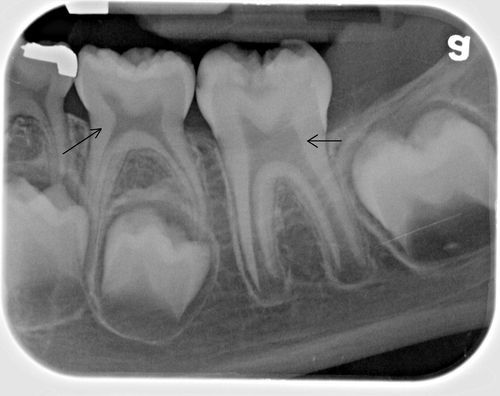

Ca dovadă că poza nu a fost prelucrată, puteţi vedea alte fotografii similare. Această radiografie, realizată de medicul stomatolog Rick Wilsond, arată măselele unui copil de 9 ani.

Deasupra gingiei sunt dinţii de lapte, iar sub gingie se pot vedea rădăcinile molarilor care vor creşte ulterior.